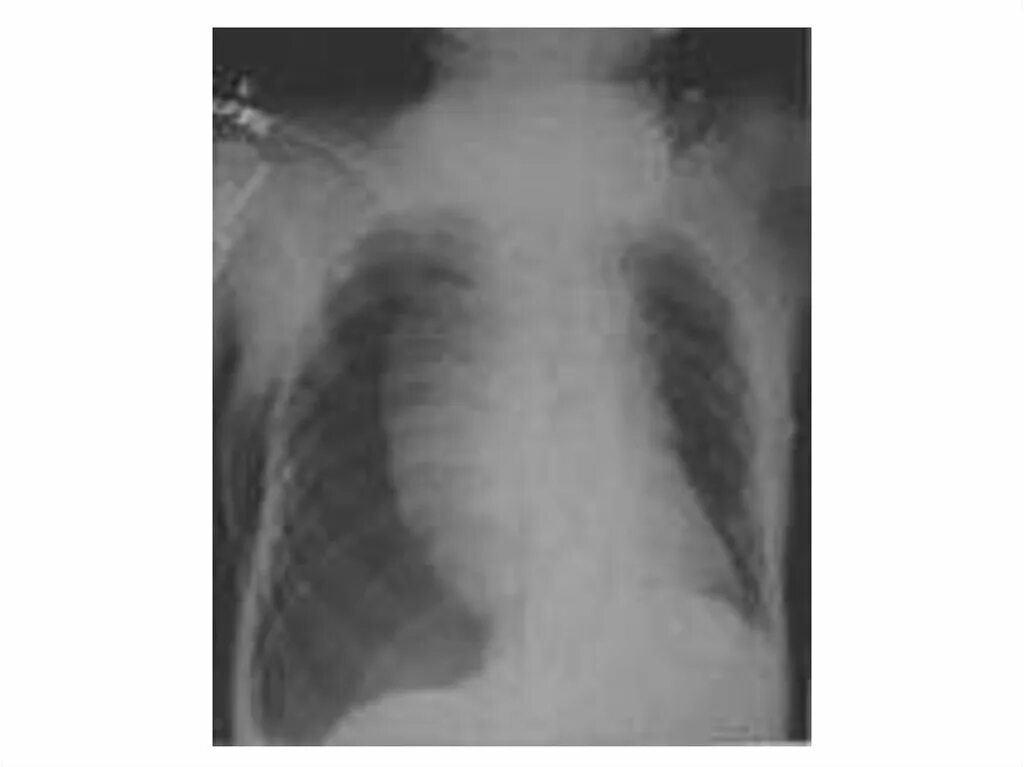

Коллабированное легкое при пневмотораксе